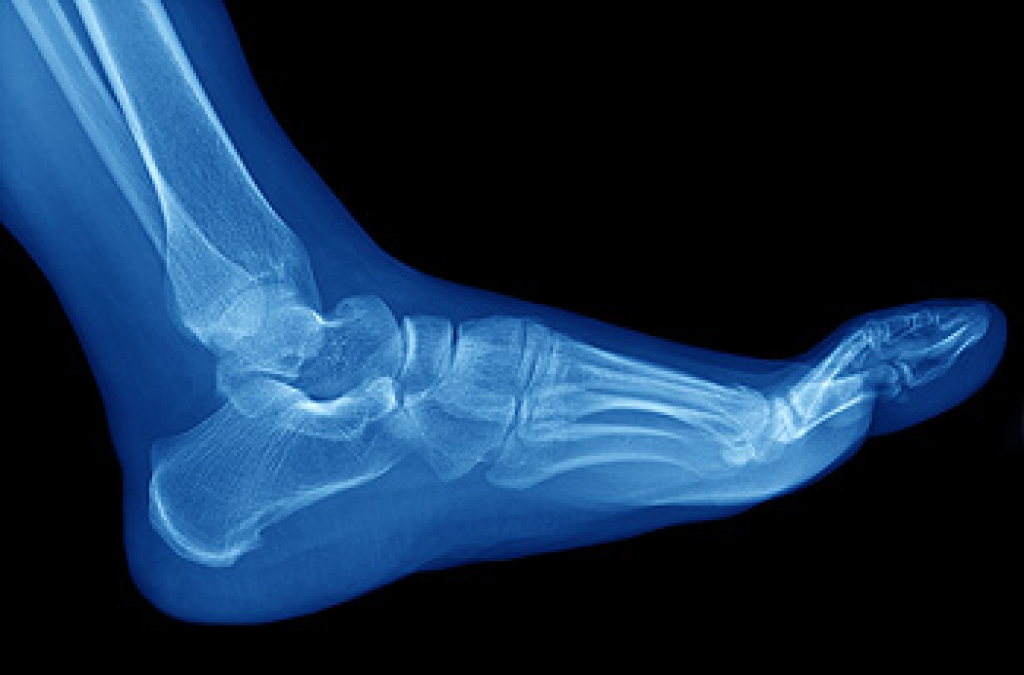

Podiatrists play a vital role in preventing falls among the elderly population in various ways. A couple of important ways they can help is by assessing footwear and prescribing custom foot orthotics. Wearing proper footwear can significantly improve balance and gait, offering better stability and reducing the risk of falls. Since many older adults wear improperly fitting shoes, a podiatrist can recommend appropriate footwear, including shoes with good traction suited to various conditions, and modifying existing shoes for a better fit. Custom foot orthotics are designed to support the feet and enhance feedback to the brain, which improves balance. They can accommodate different foot shapes and deformities, making each step more comfortable and stable, thus reducing the risk of falls. If you are elderly and want to ensure that you are doing all you can to prevent falling, it is suggested that you make an appointment with a podiatrist who can evaluate your situation and provide the help you are seeking.

Every 11 seconds, an elderly American is being treated in an emergency room for a fall related injury. Falls are the leading cause of head and hip injuries for those 65 and older. Due to decreases in strength, balance, senses, and lack of awareness, elderly persons are very susceptible to falling. Thankfully, there are a number of things older persons can do to prevent falls.